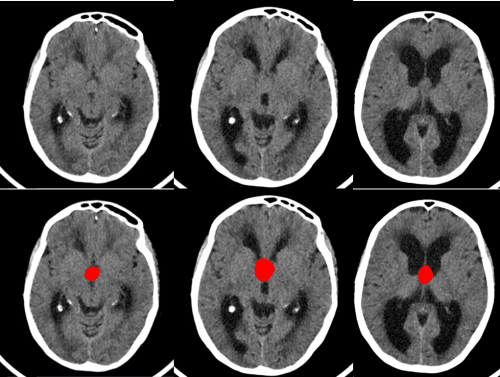

Se trata de un paciente de 63 años que comienza de forma subaguda con torpeza a la marcha y urgencia e incontinencia miccional. Acudió al servicio de urgencias donde se le realizó una TAC cerebral sin contraste (imagen 1 y 2) donde se observaba una hidrocefalia y se derivó a estudio ambulatorio con la sospecha de hidrocefalia normotensiva (imagen 2). La hidrocefalia se produce como consecuencia del aumento del líquido cefalorraquideo en el sistema ventricular cerebral o el espacio subaracnoideo.

La presentación clínica de un quiste coloide del III ventrículo puede ser la misma que la de una hidrocefalia a presión normal (alteración de la marcha, incontinencia urinaria y alteración cognitiva). Los quistes coloides del III ventrículo se suelen ver en la TAC cerebral sin contraste porque en 2/3 de las ocasiones son hiperdensos pero en 1/3 de los casos como éste caso son isodensos/hipodensos y pueden pasar desapercibidos inicialmente. Además hay que tener en cuenta que cuando se introduce contraste en la TAC cerebral puede no verse tampoco. Únicamente tras la realización de la resonancia cerebral se pudo diagnosticar por su hiperintensidad en secuencias T1 (imagen 3) y su hipointensidad en secuencias en T2.

En la imagen 4 se puede intuir la presencia del quiste coloide que inicialmente había pasado desapercibido.